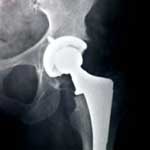

A DePuy hip lawyer filed a new lawsuit on behalf of plaintiff Bruce Pearn against the hip replacement manufacturer on October 19, 2012, in the Superior Court of Los Angeles County. The plaintiff received the DePuy ASR hip system in 2008 and had suffered from multiple problems by 2012.

Pearn states that he suffers from DePuy metal poisoning, also known as metallosis, due to the increased cobalt and ion levels in his blood. His mobility has been hindered and he has experienced emotional distress because of the complications with the implant.

Pearn believes that the DePuy ASR has created metallic debris or loosened from his acetabulum. He also believes that it detached and disconnected, causing the injuries he endures to date.